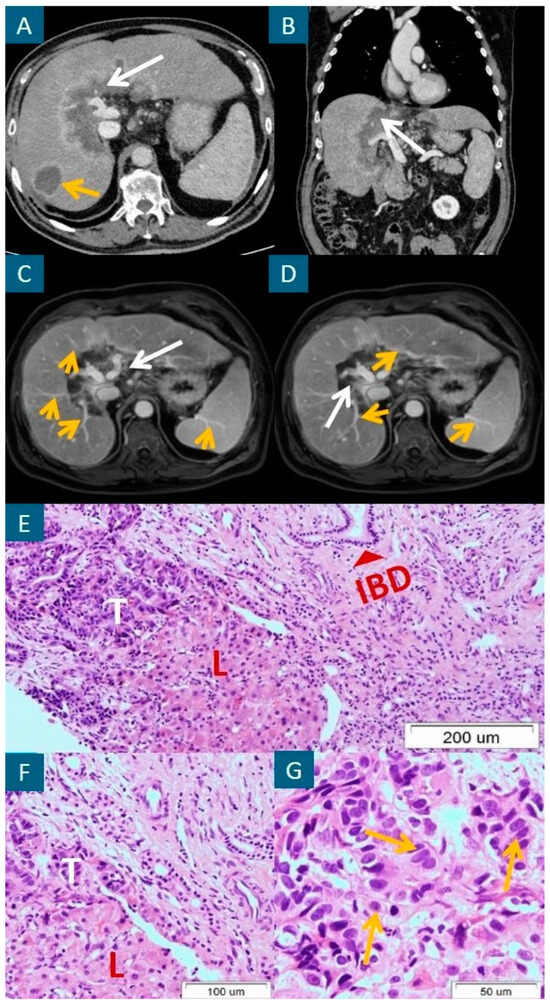

- Khandelwal, A.; Gorsi, U.; Marginean, E.C.; Papadatos, D.; George, U. Isolated Granulomatous Hepatitis-A Histopathological Surprise Mimicking Cholangiocarcinoma in Ulcerative Colitis. Ann. Hepatol. 2013, 12, 332–335. [Google Scholar] [CrossRef] [PubMed]